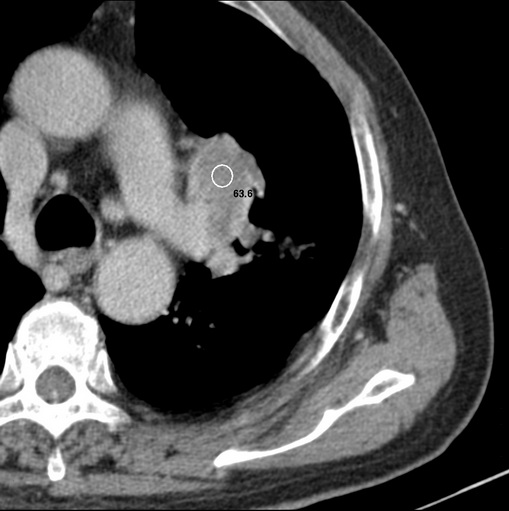

标题: CT25434:胸部CT增强扫描

男性患者 81岁 咳嗽 咳痰 咯血

有强化 考虑肺癌肺门淋巴结转移

肿块贴近左肺门,包绕左上肺动脉,形态不规则。肿块增强扫描中度强化。纵膈内主动脉弓左旁间隙、气管隆突前、下间隙见多枚淋巴结影。综上考虑左侧中央型肺癌可能性大。图片没有完整上传,尤其是左肺上叶支气管分支层面没有上传,因此不好判断是叶支气管中断还是段支气管中断。另外,下图红色部分所示是“黏液支气管征”吗?